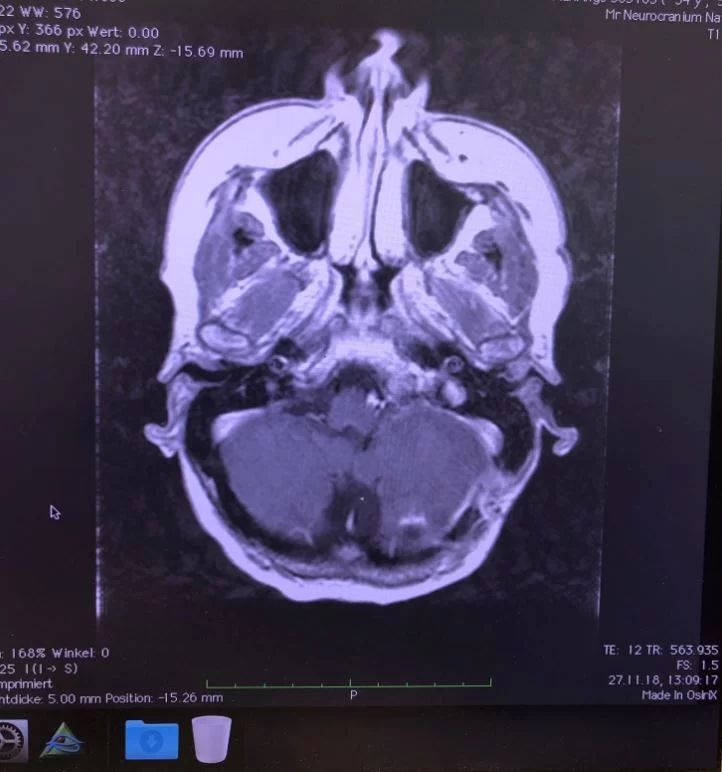

Ο προεγχειρητικός έλεγχος ανέδειξε μηνιγγίωμα της κρανιοαυχενικής συμβολής με εγκολεασμό σημαντικών αγγειακών και νευρικών δομών και επέκταση προς την αντίθετη πλευρά.

Η μετεγχειρητική μαγνητική τομογραφία εγκεφάλου δείχνει ένα εξαιρετικό αποτέλεσμα, με πλήρη αφαίρεση της βλάβης. Η ιστολογική εξέταση επιβεβαίωσε τη διάγνωση (μηνιγγίωμα WHO I).